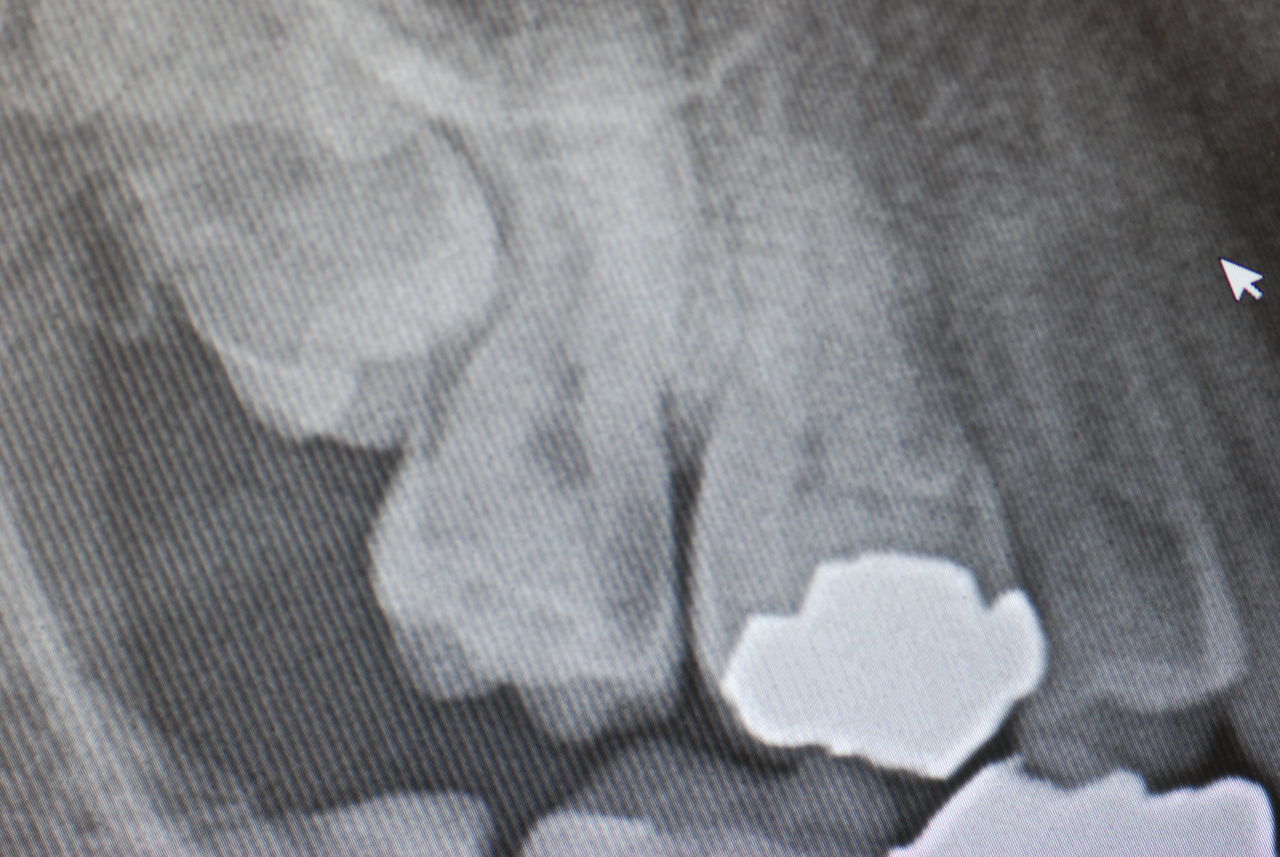

明らかにレントゲン的に奥歯の歯の間のひどい虫歯を指摘され、歯周病もありましたのでブラシの使い方をお話しして帰っていただきました。

シミテ仕方ないとのことでした。あまりにも深い虫歯でしたので残念ながらすべて除去をあきらめ、除去できるだけ除去して危ない所の除去をあきらめて抗菌的、知覚過敏を軽減するセメントを挿入してその後硬いプラスチックで閉鎖いたしました。

長くて一週間もしないうちに症状は消えますし、当日もあまり症状はなく、少し感じるぐらいに軽減したようです。大きく削らなくては歯の間の真横に進行するバイキンによる硬い歯の破壊されたところは除去できないのです。

写真は典型的な取り残したまま銀歯を入れていた方のものです。よくぞ痛くならなかったものです。

意外と手間取り一時間以上かかりセメントを入れてとりあえず終了いたしました。神経が近いので傷つけて損傷すると助かる見込みが少なくなり、痛みが出て死んでしまうとか膿んでしまうこともあるのです。![570b1c06-s[1]](https://livedoor.blogimg.jp/netdental/imgs/6/0/60221eb2.jpg)